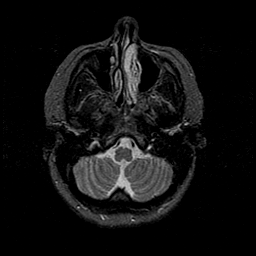

MR Study #1 -- Slice #11

[Home][Help][Clinical][Tour 1][Tour 2][Tour 3] Slice 11